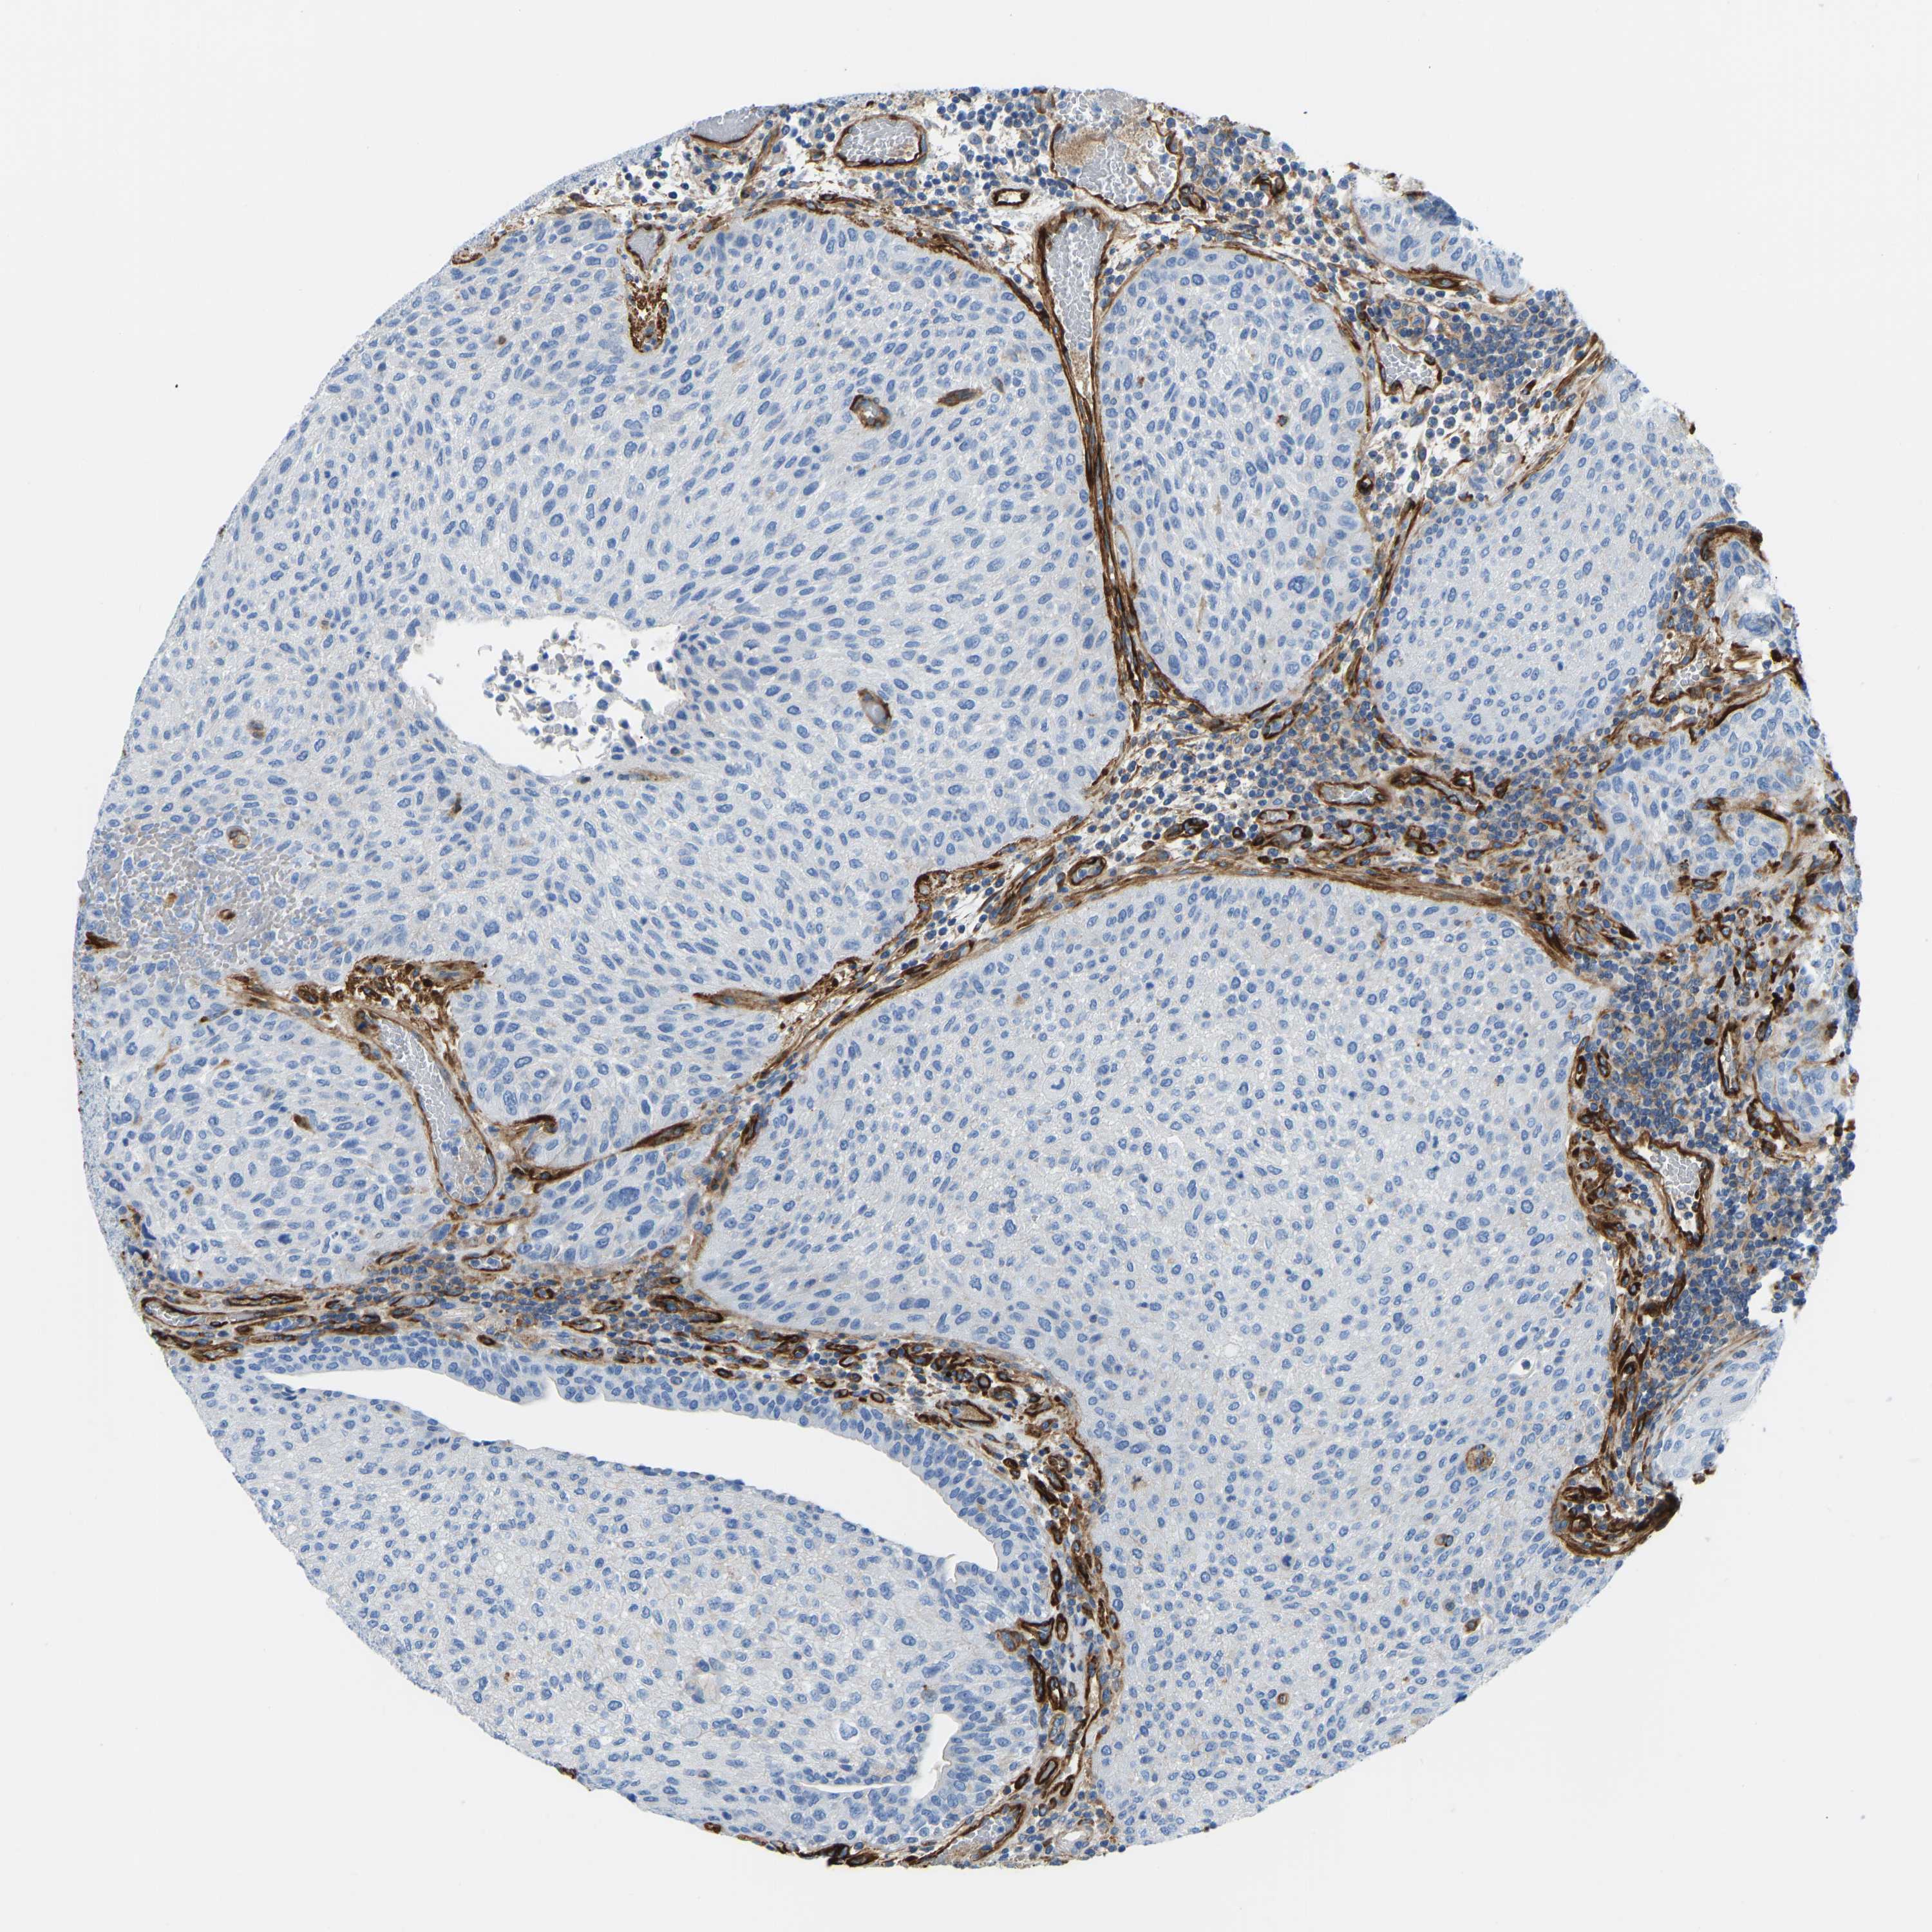

UROTHELIAL CANCER - Protein expressioni

A mouse-over function shows sample information and annotation data. Click on an image to view it in a full screen mode. Samples can be filtered based on level of antibody staining by selecting one or several of the following categories: high, medium, low and not detected. The assay and annotation is described here.

Antibody stainingi

Antibody staining in the annotated cell types in the current human tissue is reported as not detected, low, medium, or high, based on conventional immunohistochemistry profiling in selected tissues. This score is based on the combination of the staining intensity and fraction of stained cells.

Each image is clickable and will lead to virtual microscopy that enables deeper exploration of all samples and also displays staining intensity scores, fraction scores and subcellular localization as well as patient and tissue information for each sample.

Antibody HPA017913

Antibody HPA017915

Staining

High

Medium

Low

Not detected

Intensity

Strong

Moderate

Weak

Negative

Quantity

>75%

75%-25%

<25%

None

Location

Nuclear

Cytoplasmic/membranous

Cytoplasmic/membranous,nuclear

Urothelial carcinoma, Low grade

Urothelial carcinoma, High grade